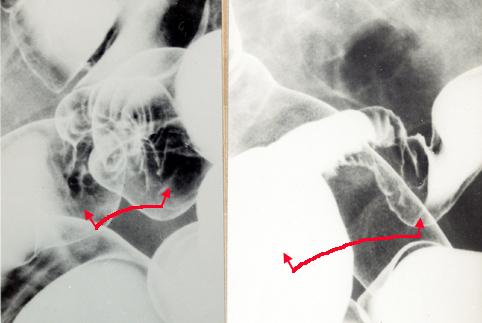

Endometriosis causado por canal intestinal, que fue operado por motivo constricción de Colon Signoides.

Lesión que asemeja tumoración/Mucosa aberrante

colon/sigmoides

Rayos X

40 -